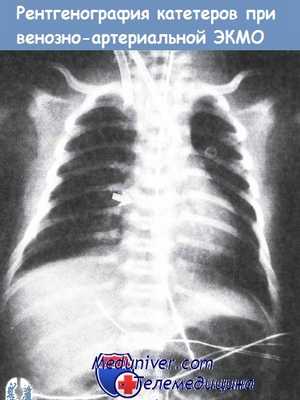

Правильное расположение артериального и венозного катетеров при рентгенографии.

Видна рентгеноконтрастная точка, обозначающая кончик катетера для экстракорпоральной мембранной оксигенациии марки «Bio-Medicus» (указана стрелкой).